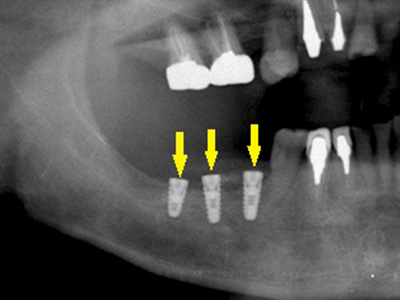

骨移植手術数か月後に、移植した骨片が周囲骨に生着したので、インプラントを埋入した時のレントゲン写真です。

十分な骨量が確保されていましたので、下方を走行する神経を損傷することなく埋入が可能になりました。 -